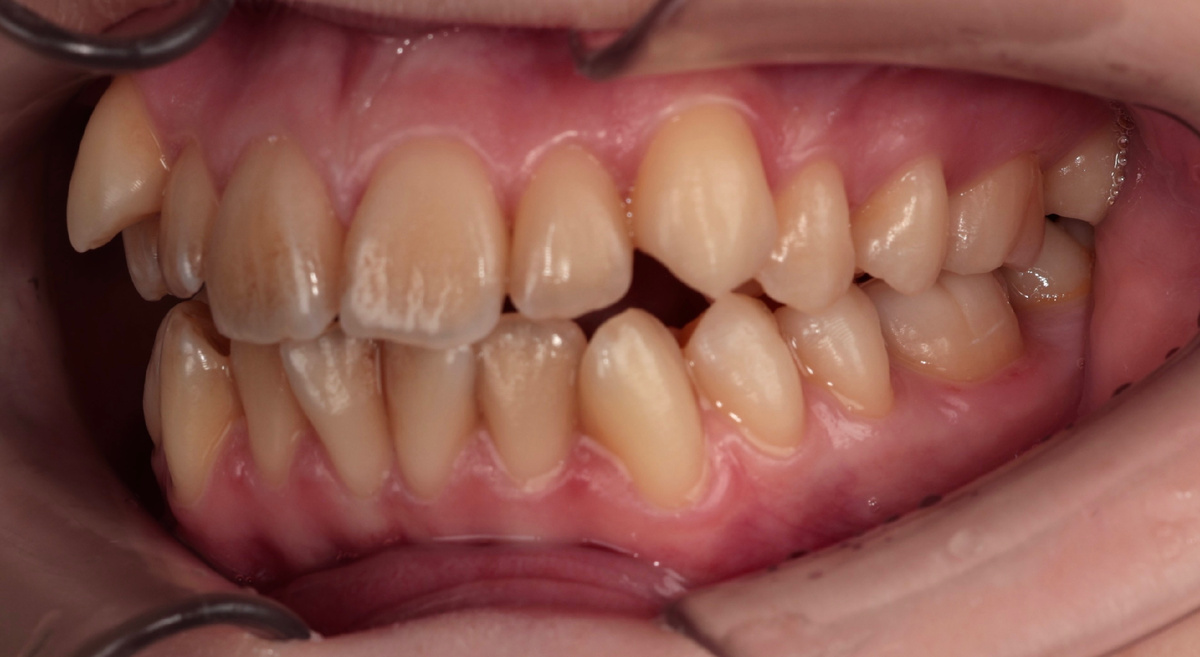

Результат перемещения клыков с вестибулярным супраположением за три месяца

Посмотрите на фото "до" и "после 3 месяцев". Разница очевидна даже неспециалисту. Клыки из положения "дракула" перешли в положение "почти нормально".

Кто-то увидит результат и спросит: - "Может, уже снимать пора? Красиво же!"

Нет, нельзя! Это только 20% пути. Визуально красиво, функционально - ещё нужно работать.